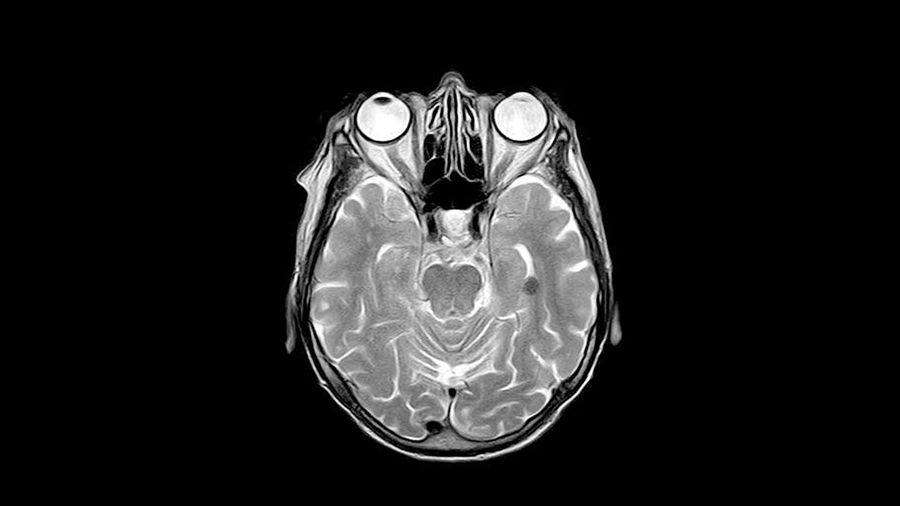

Strålning är det kanske effektivaste verktyget för att behandla elakartade hjärntumörer. Men strålningen ger samtidigt ofta upphov till svåra sena komplikationer, som svårigheter med inlärning och minne och nedsatt intellektuell förmåga, i synnerhet hos barn.

I en ny artikel som publiceras i den vetenskapliga tidskriften Cell Reports beskriver forskare hur effekterna av strålning av en ung hjärna skiljer sig från en vuxens.

I försök på möss har man sett att det sker en kraftig inflammation i hjärnan cirka sex timmar efter strålning, hos både vuxna och unga. Det är mikroglia, hjärnans immunceller, som reagerar våldsamt efter strålning. Ganska snart går inflammationen ner, men därpå följer en kronisk inflammation som bryter ner hjärnan och gör att den åldras snabbare och bidrar till de sena komplikationer som uppstår.